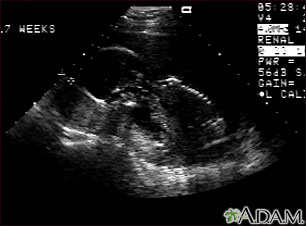

Ultrasound, normal fetus - profile view

This is a normal fetal ultrasound performed at 17 weeks gestation. In the middle of the screen, the profile of the fetus is visible. The outline of the head can be seen in the left middle of the screen with the face down and the body in the fetal position extending to the lower right of the head. The outline of the spine can be seen on the right middle side of the screen.